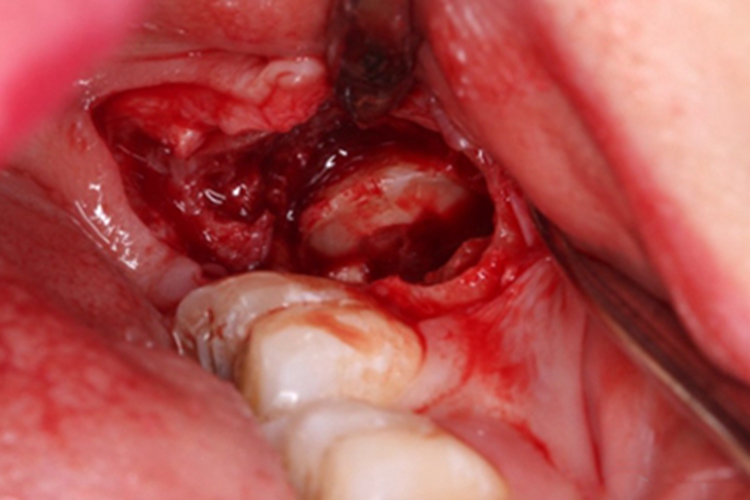

拔除阻生牙

当邻牙阻力及骨阻力解除后,即可使用牙挺及牙钳顺利拔除分好的阻生牙,并应将拔除的牙体组织拼对检查是否完整,避免遗留残片。